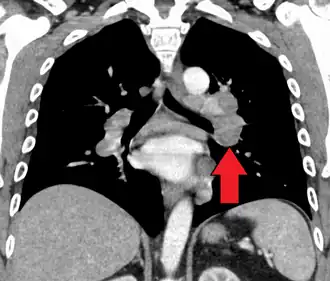

CT scan of the chest showing lymphadenopathy (arrows) in the mediastinum due to sarcoidosis

Diagnosis of sarcoidosis is a matter of exclusion, as there is no specific test for the condition other than the Kveim-Siltzbach test. To exclude sarcoidosis in a case presenting with pulmonary symptoms might involve a chest radiograph, CT scan of chest, PET scan, CT-guided biopsy, mediastinoscopy, open lung biopsy, bronchoscopy with biopsy, endobronchial ultrasound, and endoscopic ultrasound with fine-needle aspiration of mediastinal lymph nodes (EBUS FNA). Tissue from biopsy of lymph nodes is subjected to both flow cytometry to rule out cancer and special stains (acid fast bacilli stain and Gömöri methenamine silver stain) to rule out microorganisms and fungi.[99][100][12][101]